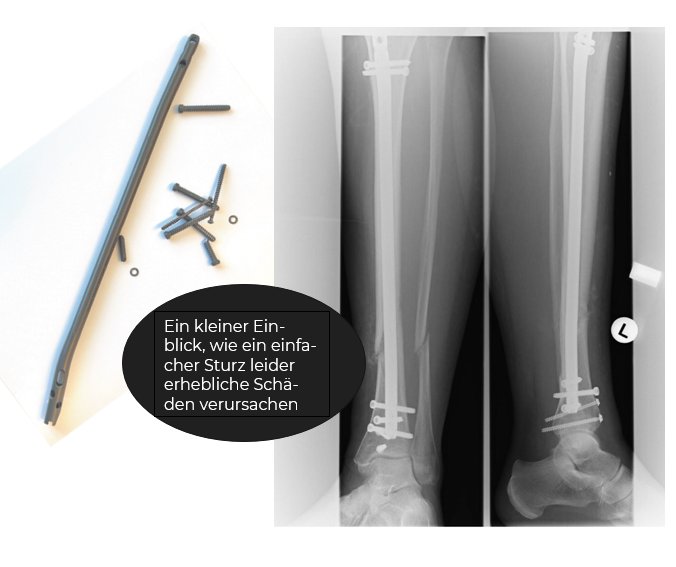

Im Krankenhaus folgte die nächste Hiobsbotschaft: Eine komplizierte Fraktur des linken Unterschenkels und ein Bruch im Sprunggelenk. Noch am gleichen Tag führte der Chefarzt die Not-OP durch. Ein 30 cm langer Nagel wurde im Schienbein verschraubt, um die Knochen wieder zusammenzubringen. Gisela musste eine Woche im Krankenhaus bleiben, aber das war erst der Anfang der Odyssee.